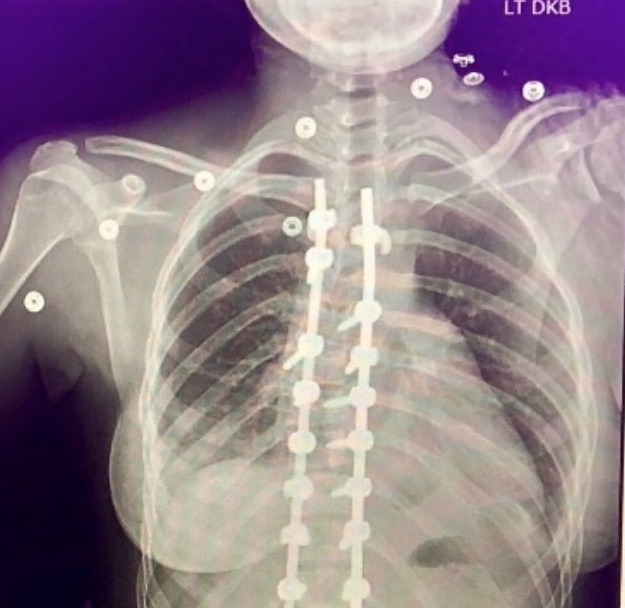

I was scared I had messed up spine. And for those who don’t know I underwent a spinal fusion 6-7 years ago. Something I found out when I got older was that I could re-injure my back at any time.